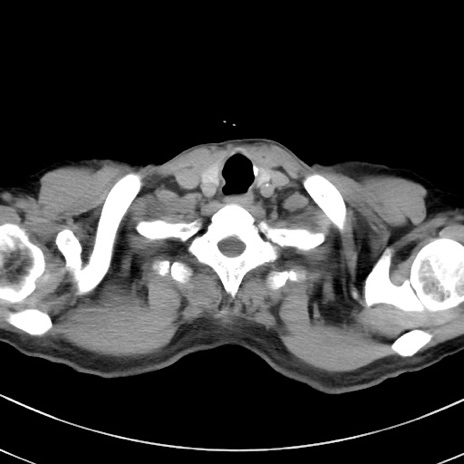

症例38(横断像)

【症例】70歳代 男性

【主訴】腹痛・嘔吐

【現病歴】昨晩より、嘔吐・腹痛あり。今朝になっても嘔吐あり。来院。

【既往歴】心臓バイパス手術、開腹胆摘、腸閉塞

【身体所見】BP 107/71mmHg、HR 116/min、腹部:平坦、軟、下腹部に軽度圧痛あり。反跳痛なし。

【データ】WBC 15100、CRP 0.32